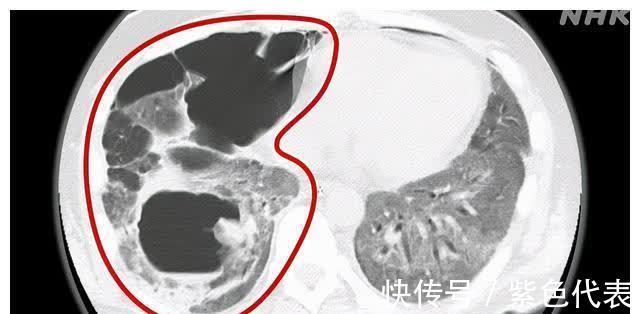

和手术前不同,这次肺内侧出现了黑色空洞。炎症扩散到整个肺部,内部的组织也被破坏了。而发生这一切的原因不是病毒。

如果感染了新型冠状病毒,人体免疫系统为保护人体不受伤害,就不断释放免疫细胞前往病处,但人体自身的免疫细胞会有很大概率发生“暴走”,甚至会攻击人体自身。这是被认为是患者重症化的主要原因之一,而患者的肺部炎症也正是符合了这一原因。

从影像上可以看到,患者的肺部空洞很大,这次要做手术也很困难。而多数医生建议进行“肺移植”。